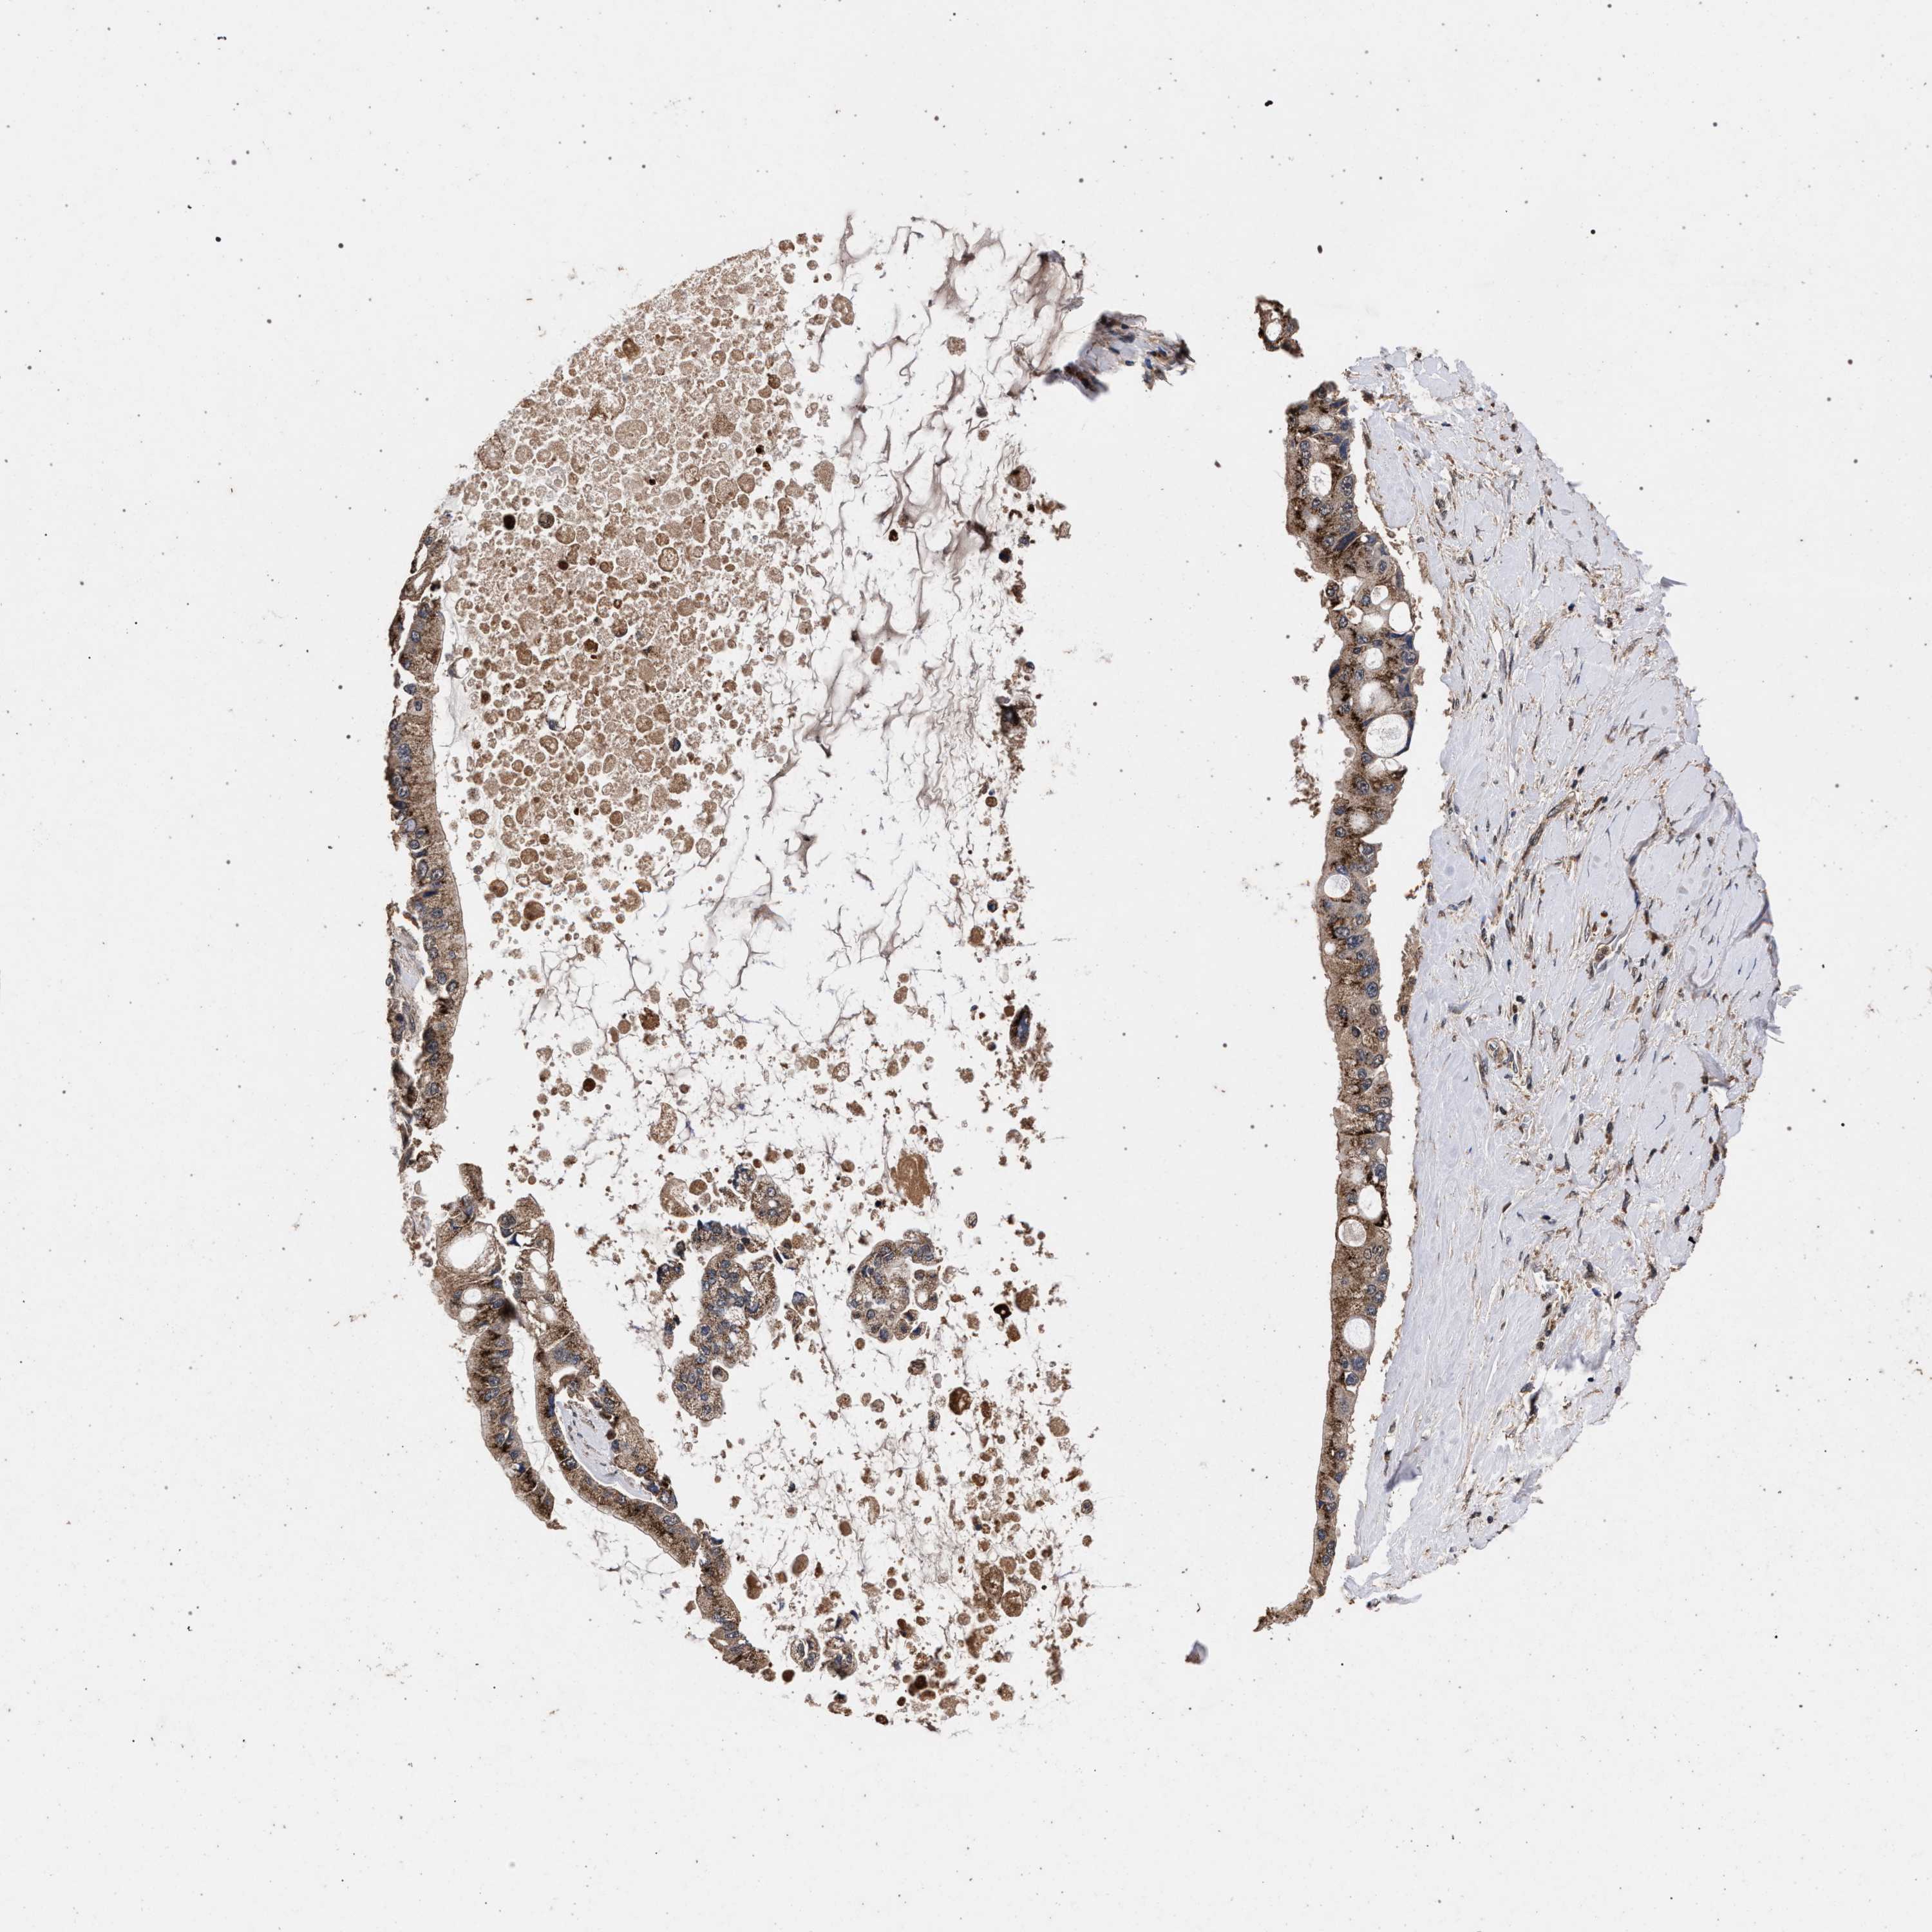

LIVER CANCER - Protein expressioni

A mouse-over function shows sample information and annotation data. Click on an image to view it in a full screen mode. Samples can be filtered based on level of antibody staining by selecting one or several of the following categories: high, medium, low and not detected. The assay and annotation is described here.

Note that samples used for immunohistochemistry by the Human Protein Atlas do not correspond to samples in the TCGA dataset.

Antibody stainingi

Antibody staining in the annotated cell types in the current human tissue is reported as not detected, low, medium, or high, based on conventional immunohistochemistry profiling in selected tissues. This score is based on the combination of the staining intensity and fraction of stained cells.

Each image is clickable and will lead to virtual microscopy that enables deeper exploration of all samples and also displays staining intensity scores, fraction scores and subcellular localization as well as patient and tissue information for each sample.

Antibody HPA021192

Antibody HPA021195

Antibody HPA028759

Antibody CAB021094

Staining

High

Medium

Low

Not detected

Intensity

Strong

Moderate

Weak

Negative

Quantity

>75%

75%-25%

<25%

None

Location

Nuclear

Cytoplasmic/membranous

Cytoplasmic/membranous,nuclear

Cholangiocarcinoma

Carcinoma, Hepatocellular, NOS